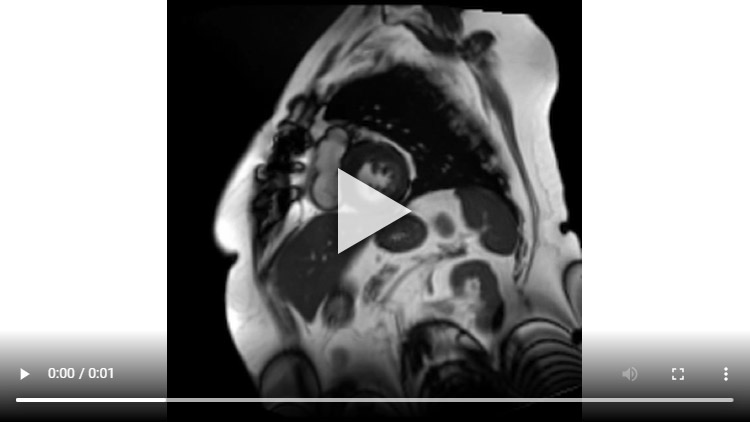

Une IRM de stress a été réalisée, et retrouve les images suivantes :

Figure 5A : Séquence Ciné-IRM

Coupes petit-axe médian

Figure 5B : Séquence Ciné-IRM

Coupes 2-cavités

Figure 5C : Séquence Ciné-IRM

4-cavités